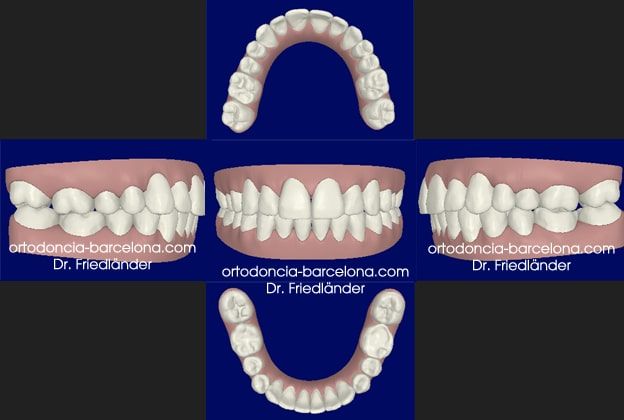

Todos los casos de Invisalign se planifican en 3D con el programa de invisalign; Clincheck; con el cual planificamos todos los aspectos del tratamiento. Antes de aceptar el plan del tratamiento se lo enseñamos la paciente y él es quien lo acepta.

Simulación del Clincheck,

Simulación del Clincheck final